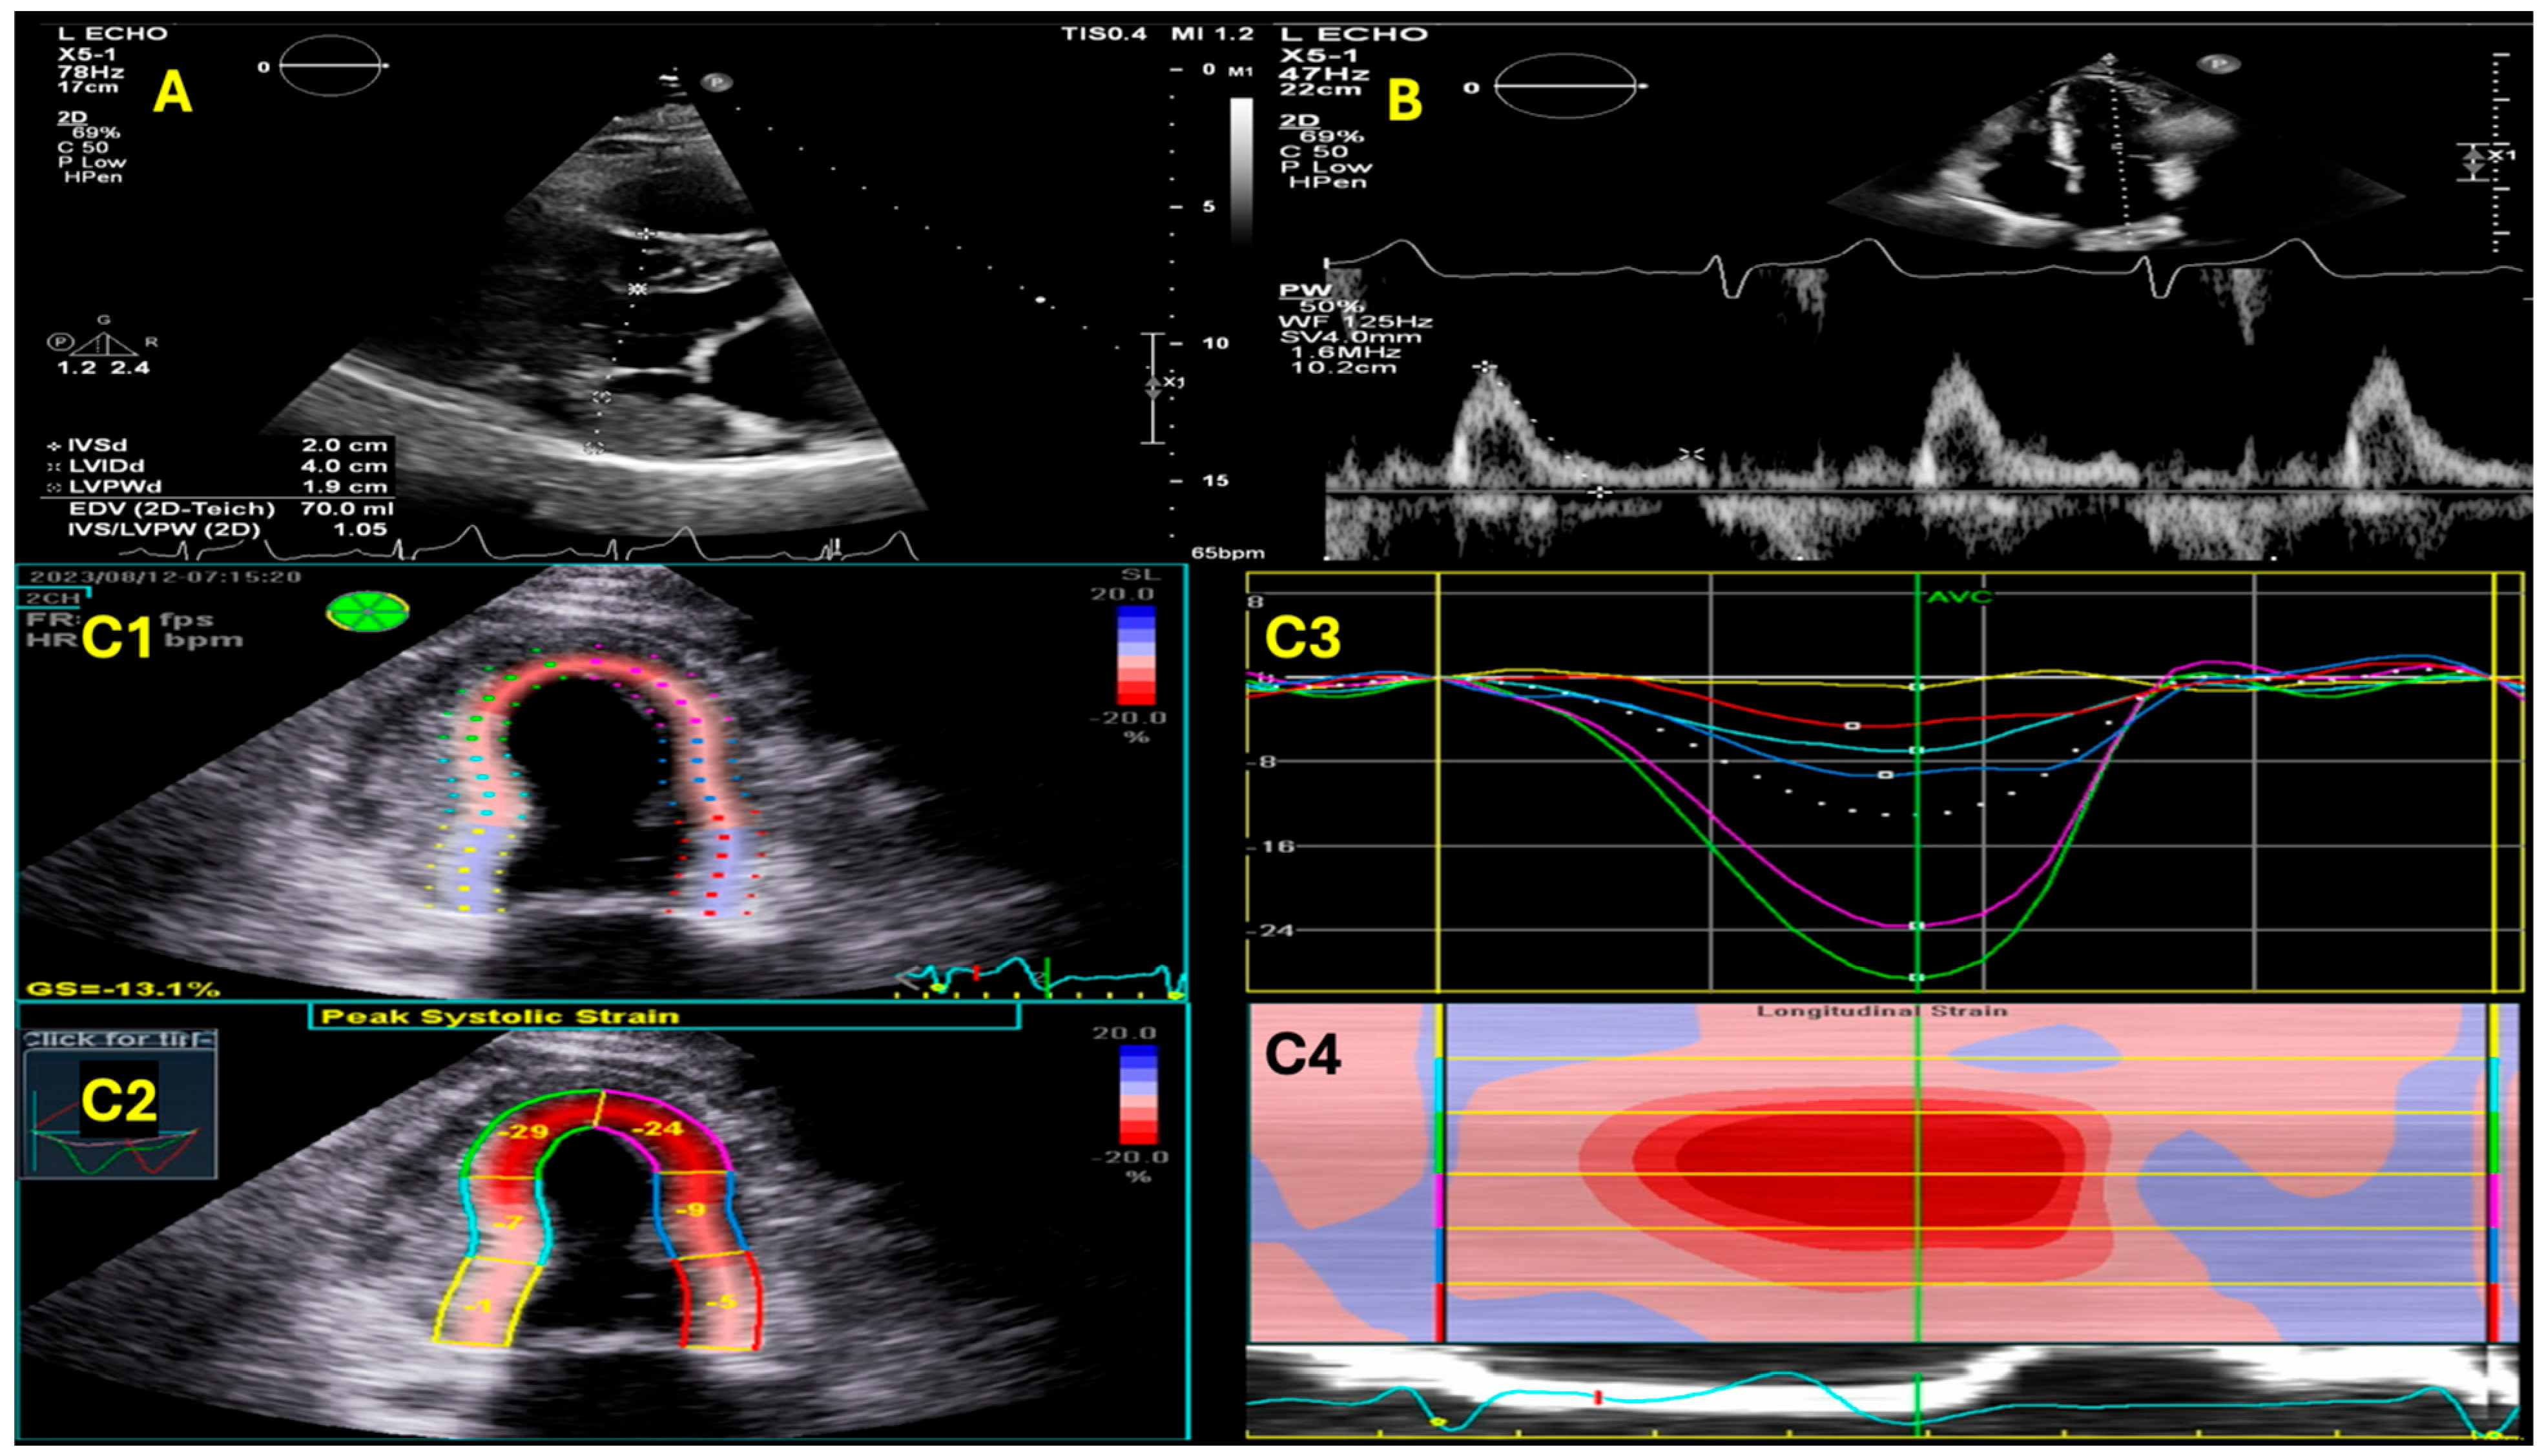

- Boldrini, M.; Cappelli, F.; Chacko, L.; Restrepo-Cordoba, M.A.; Lopez-Sainz, A.; Giannoni, A.; Aimo, A.; Baggiano, A.; Martinez-Naharro, A.; Whelan, C.; et al. Multiparametric Echocardiography Scores for the Diagnosis of Cardiac Amyloidosis. Cardiovasc. Imaging 2019, 13, 909–920. [Google Scholar] [CrossRef] [PubMed]

- Tsuruda, T.; Nakada, H.; Yamamura, Y.; Matsuura, Y.; Ogata, M.; Tanaka, M.; Suiko, Y.; Komaki, S.; Tanaka, H.; Moribayashi, K.; et al. Basal inferoseptal segment is highly susceptible to deformation in the clinical spectrum of transthyretin-derived amyloid cardiomyopathy. Eur. Heart J. Open 2024, 4, oeae076. [Google Scholar] [CrossRef]

- Knight, D.S.; Zumbo, G.; Barcella, W.; Steeden, J.A.; Muthurangu, V.; Martinez-Naharro, A.; Treibel, T.A.; Abdel-Gadir, A.; Bulluck, H.; Kotecha, T.; et al. Cardiac Structural and Functional Consequences of Amyloid Deposition by Cardiac Magnetic Resonance and Echocardiography and Their Prognostic Roles. JACC Cardiovasc. Imaging 2018, 12, 823–833. [Google Scholar] [CrossRef]